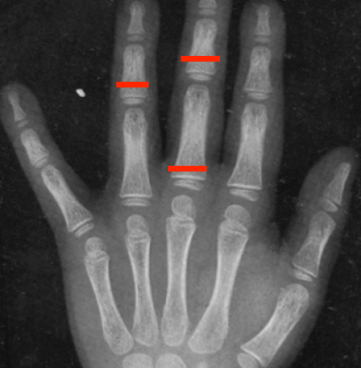

Nel sospetto di displasia scheletrica sono stati eseguiti cariotipo e analisi del gene SHOX risultati nella norma, e acquisiti radiogrammi total-body, da cui sono emersi due elementi guida: l’aspetto di deformazione conica delle falangi intermedie e prossimali (cone-shaped epiphyses) (Figura 1), associate a irregolarità metafisarie elettivamente localizzate alle ginocchia di entità lieve (aree radiopache, trabecolatura grossolana) progressivamente più evidenti nel corso degli anni. Tali caratteristiche radiologiche rappresentano aspetti altamente specifici di ipoplasia cartilagine-capelli (CHH) / osteocondrodisplasia metafisaria tipo McKusick: la diagnosi è stata poi confermata al sequenziamento del gene RMRP che ha rilevato una mutazione in doppia eterozigosi, di cui entrambi i genitori sono portatori sani.